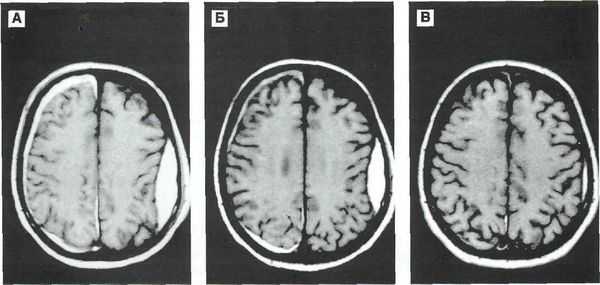

Врач может определить приблизительный возраст гематомы по снимкам компьютерной и магнитно-резонансной томографии (КТ и МРТ). От срока давности зависит выбор методов лечения.

Методом выбора при диагностике ушиба головного мозга является КТ головного мозга. На КТ определяют ограниченную зону пониженной плотности, возможны переломы костей свода черепа, субарахноидальное кровоизлияние. При ушибе мозга средней степени тяжести на КТ или спиральной КТ в большинстве случаев выявляют очаговые изменения (некомпактно расположенные зоны пониженной плотности с небольшими участками повышенной плотности).

При ушибе тяжелой степени на КТ определяются зоны неоднородного повышения плотности (чередование участков повышенной и пониженной плотности). Перифокальный отек головного мозга сильно выражен. Формируется гиподенсивная дорожка в область ближайшего отдела бокового желудочка. Через нее происходит сброс жидкости с продуктами распада крови и мозговой ткани.

Решающими методами в диагностике субдуральной гематомы являются КТ и МРТ головного мозга. В диагностике острых гематом предпочтение отдается КТ головного мозга, которая в таких случаях выявляет однородную зону повышенной плотности, имеющую серповидную форму. С течением времени происходит разуплотнение гематомы и распад кровяных пигментов, в связи с чем через 1-6 нед. она перестает отличается по плотности от окружающих тканей. В подобной ситуации диагноз основывается на смещении латеральный отделов мозга в медиальном направлении и признаках сдавления бокового желудочка.

При проведении МРТ может наблюдаться пониженная контрастность зоны острой гематомы; хронические субдуральные гематомы, как правило, отличаются гиперинтенсивностью в Т2 режиме. В затруднительных случаях помогает МРТ с контрастированием. Интенсивное накопление контраста капсулой гематомы позволяет дифференцировать ее от арахноидальной кисты или субдуральной гигромы.